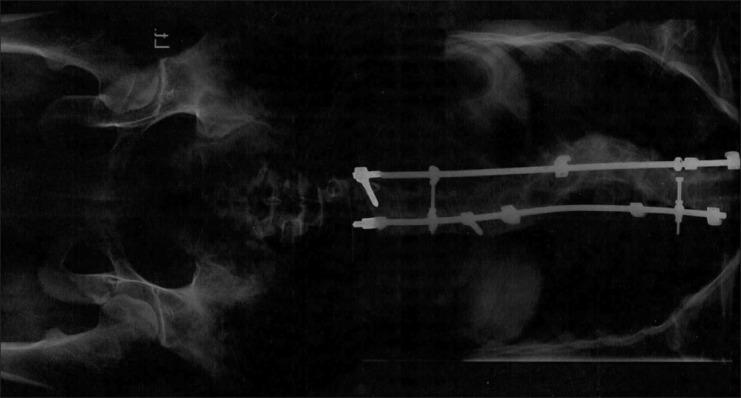

The term neurofibromatosis (NF) is used for a group of genetic disorders that primarily affect the cell growth of neural tissues. Neurofibromatosis type 1 (NF1), also known as von Recklinghausen's disease, is the most common type of NF, and accounts for about 90% of all cases. It is one of the most frequent human genetic diseases, with a prevalence of one case in 3,000 births. The expressivity of NF1 is extremely variable, with manifestations ranging from mild lesions to several complications and functional impairment. Oral manifestations can be found in almost 72% of the NF1 patients. The aim of this article is to report the NF1 in a family with different manifestations and to review the literature.

神经纤维瘤病(NF)一词用于指代一组主要影响神经组织细胞生长的遗传性疾病。1型神经纤维瘤病(NF1),也称为冯·雷克林豪森病,是最常见的NF类型,约占所有病例的90%。它是最常见的人类遗传病之一,发病率为每3000例出生中有1例。NF1的表现极为多样,从轻微病变到多种并发症和功能障碍都有。几乎72%的NF1患者会出现口腔表现。本文旨在报告一个具有不同表现的NF1家系并对文献进行综述。